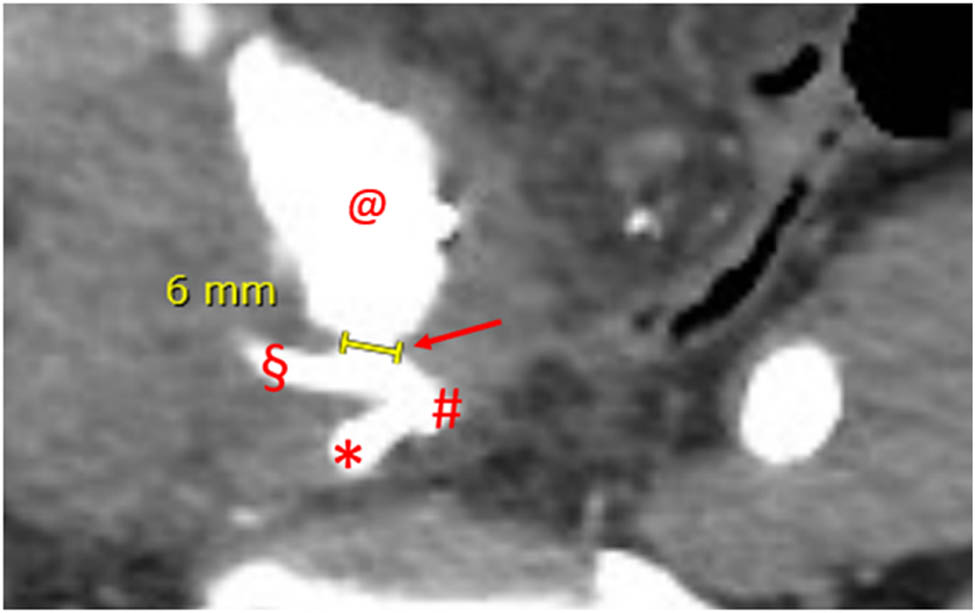

Figure 2

Angio-CT, axial plane, arterial phase, case 1. Major diameter of the UAF. Dart: UAF with concomitant iodinated contrast leakage; #: common right iliac artery bifurcation; *: hypogastric artery; §: external iliac artery; and @: pseudoaneurysm sac.

Subiela et al. reported the number and type of diagnostic techniques used in the most recent studies from 1990 to 2017: the prevalence of angiography and angioTC employment was 36.2 and 29.8%, respectively, but the authors did not refer their diagnostic accuracy. However, the authors stated that CT scan with contrast was the most used and accurate method for the diagnosis of UAF [10]. In our first case, the indication for CT scan was mandatory due to the lipothymic-neurological signs that anticipated the severe haemorrhagic shock. CT scan in this case was diagnostic, and angiography only confirmed and targeted the fistula for the endovascular treatment. The antegrade pyelography carried out after endovascular treatment was purely descriptive. The positivity of all radiological exams is certainly attributable to the size of the fistula (6 mm in maximum diameter) which, in the acute phase of rupture, determined a blood outflow of about 7 mL/s, considering that usually the speed of blood flow at the level of the iliac artery is about 30 cm/s.